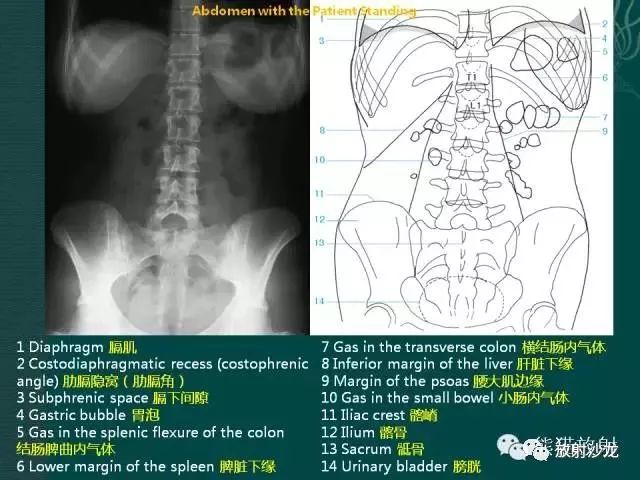

1

腹部平片解剖

2

腹部平片正常表现